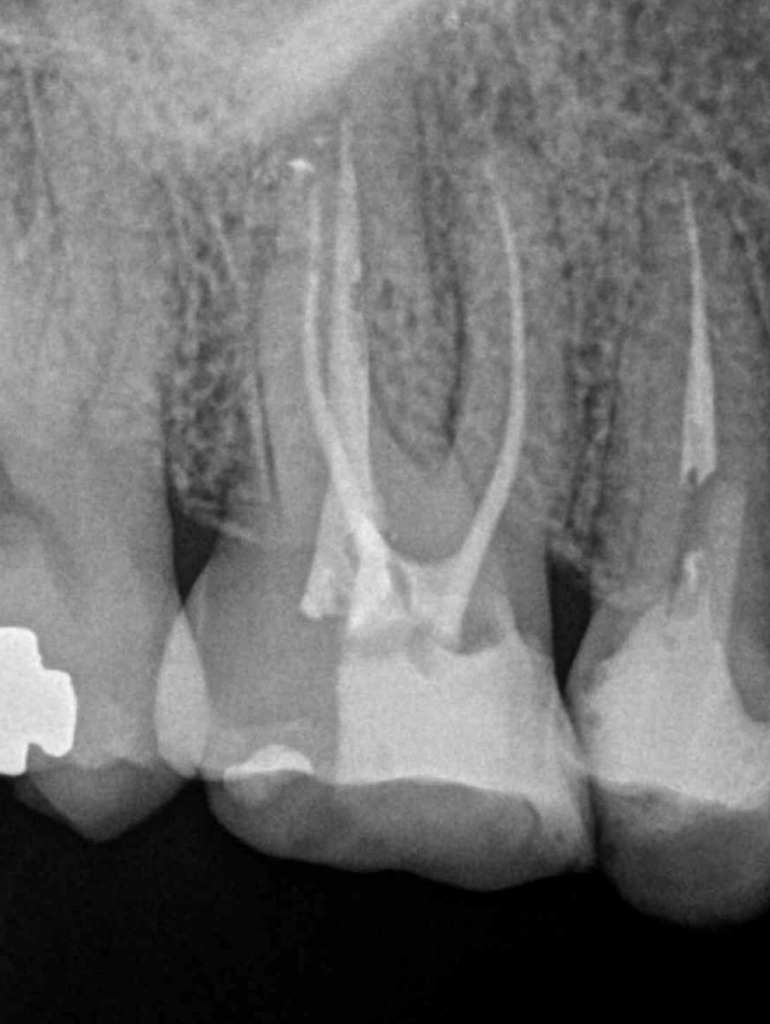

Reco preendo + 4 conductos molar superior